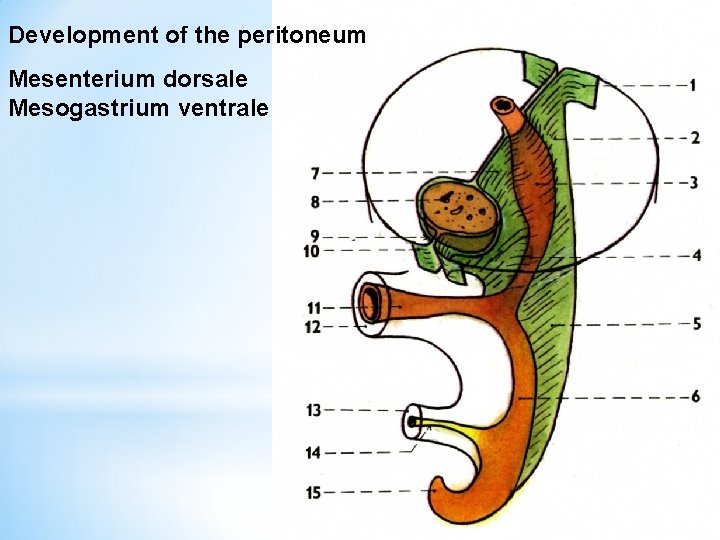

Development of the peritoneum Mesenterium dorsale Mesogastrium ventrale